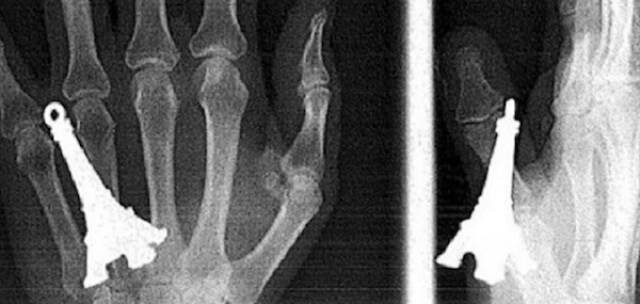

15. Модель Эйфелевой башни в руке